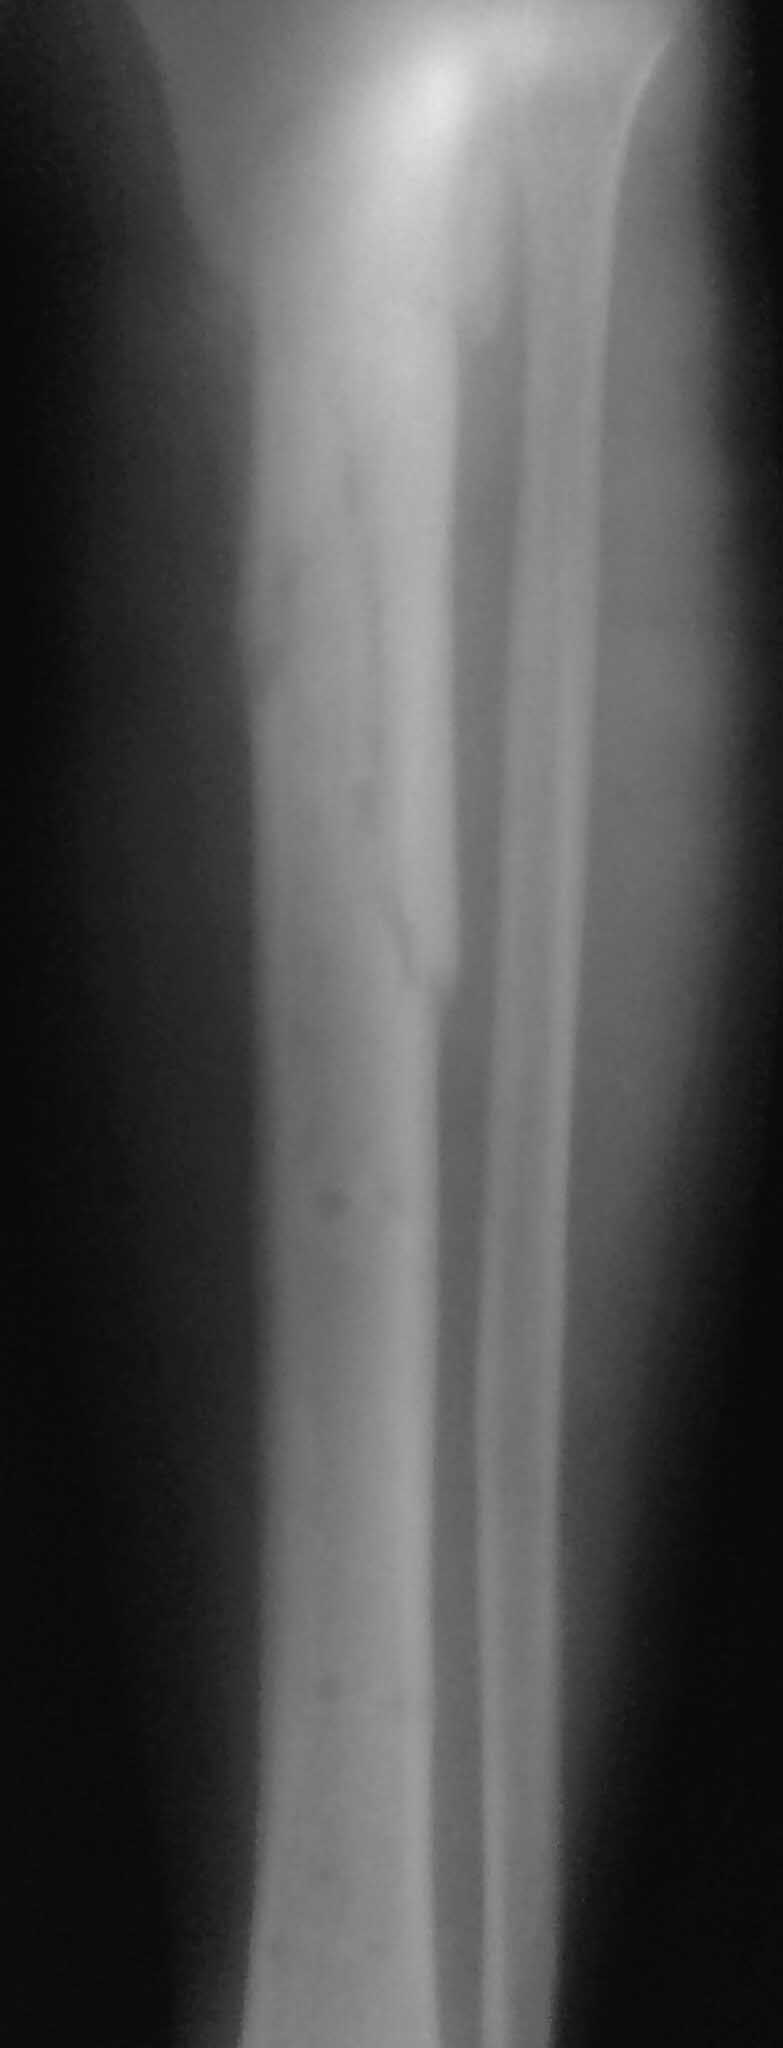

Все таки решились на штифт с антибиотическим покрытием. Выставляю R, в целом считаю неплохо вроде получилось.

Спасибо за обсуждение.Отправил остальные R, изиняюсь за качество.

3.Перелом на 2 уровнях, есть искривление костно-мозгового канала. Проксимальный отломок короткий.